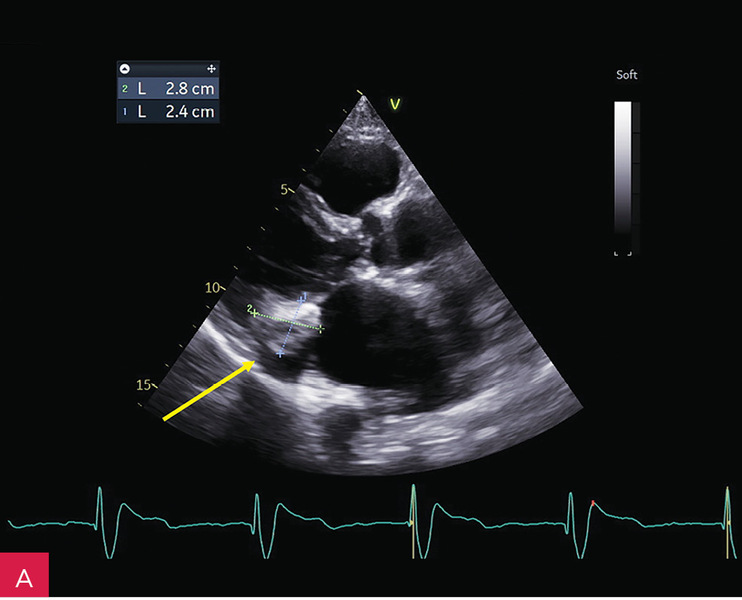

W badaniu echokardiograficznym przezklatkowym (TTE – transthoracic echocardiography) uwidoczniono guzowatą zmianę o wymiarach 37 × 28 × 25 mm u podstawy tylnego płatka zastawki mitralnej i w obrębie ściany dolno-bocznej lewej komory, o nierównej powierzchni od strony komory, nieznacznej ruchomości zgodnej z ruchem serca i niejednorodnej echostrukturze ze zwapnieniami (ryc. 2-5). Powodowała ona niewielkie ograniczenie ruchomości płatków zastawki mitralnej z utrudnieniem napełniania komory i parametrami małej stenozy (ryc. 6). Stwierdzono ponadto małą niedomykalność mitralną (ryc. 6), dużą niedomykalność trójdzielną, znacznie powiększone obydwa przedsionki oraz w niewielkim stopniu prawą komorę w zakresie drogi odpływu, a także niewielki przerost ścian lewej komory. W badaniu nie stwierdzono wyraźnych odcinkowych zaburzeń kurczliwości lewej komory. Globalna funkcja skurczowa lewej i prawej komory była zachowana w dolnych granicach normy: frakcja wyrzutowa lewej komory (LVEF – left ventricular ejection fraction) 50%, skurczowe przemieszczenie płaszczyzny pierścienia trójdzielnego (TAPSE – tricuspid annular plane systolic excursion) 18 mm. Stwierdzono cechy dysfunkcji rozkurczowej lewej komory z cechami wysokiego ciśnienia napełniania. Zarejestrowano również małą ilość płynu w osierdziu (do 6 mm za ścianą boczną lewej komory).

Rycina 9A-C. Kontrolne badanie echokardiograficzne przezklatkowe (TTE) po 5 miesiącach od rozpoznania uwidoczniło porównywalne wymiary zmiany guzowatej jak w badaniu wyjściowym (A), brak progresji zwężenia zastawki mitralnej (B), charakterystyczny obraz uwapnionej otoczki z bezechowym rdzeniem wewnętrznym (C)